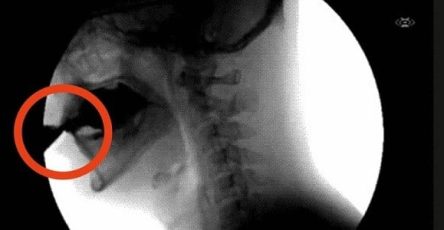

A stroke is a medical emergency that occurs when blood flow to the brain is interrupted, causing brain damage, disability, or even death. The good news is that the body often sends warning signals up to 15 minutes before a stroke occurs.